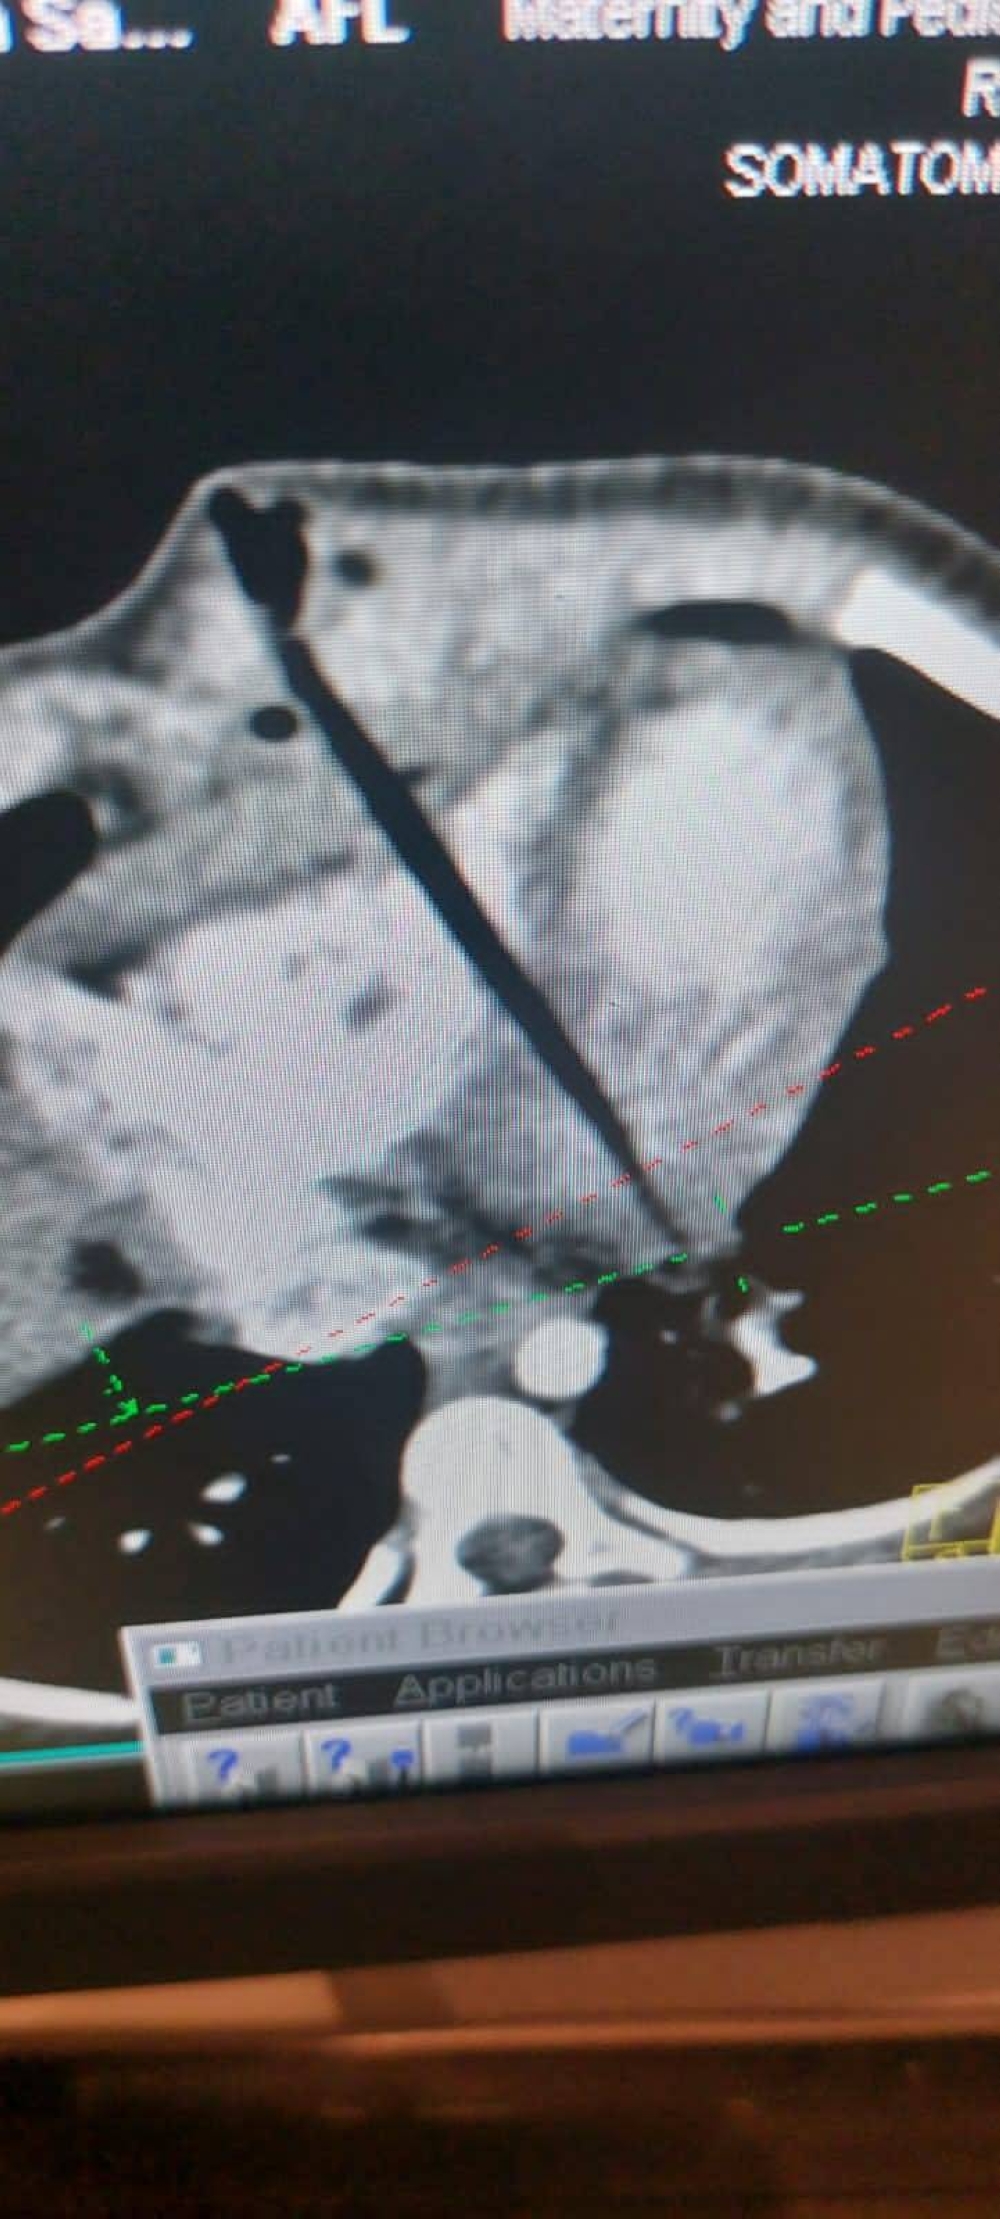

وبيّنت المدينة أن الفريق الطبي نجح في العملية الجراحية العاجلة بكفاءة واحترافية عالية فور وصول الطفلة لطورائ مدينة الملك فهد الطبية وتكوّن من جراحي القلب والأشعة التداخلية وفريق الإيكمو وفريق التخدير، حيث تم عمل الأشعة المقطعية لمتابعة تقييم الفرق الطبية ونقلها مباشرة لغرفة العمليات وإزالة القطعة الخشبية من منطقة الصدر والقلب بنجاح.

وذكرت المدينة أنه بعد العملية تم عمل أشعة قلبية للطفلة لمراقبة القلب والثقوب الناتجة وتقييم المنقطة المتضررة للتأكد من الوضع الصحي.